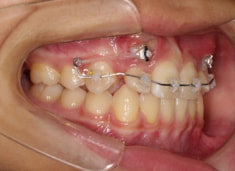

治療開始時

FX(フェイシャルアキシス)は85度なので東洋人の平均値に近く、下顎が前方に過剰成長するリスクは強くはありません。

しかしやはり上顎は劣成長で、下顎が優位な状態ではあります。

上下顎のギャップはありますが、顔面自体の幅径は良好な値を示していますので、スペース不足は拡大することによって解決できポテンシャルはあると考えられます。